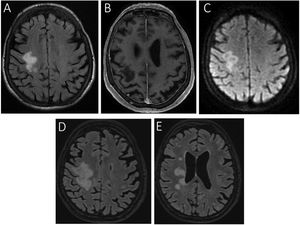

Imágenes de RM craneal potenciadas en axial T2 FLAIR, T1 gadolinio y difusión.

La imagen en corte axial FLAIR (A), T1 gadolinio (B) y difusión (C) en el momento del primer ingreso de la paciente muestra una alteración de señal en la región perirrolándica derecha, con extensión al centro semioval. No se observa realce tras la administración de contraste y la difusividad se encuentra aumentada. Dos meses después (D) se observa un crecimiento de la lesión inicial, con extensión al cuerpo calloso y a la cápsula interna, además de apreciarse pequeñas lesiones satélites en la sustancia blanca adyacente (E).

En marzo de 2020, una mujer de 74años ingresó en nuestro hospital por debilidad muscular progresiva en la extremidad superior izquierda de dos meses de evolución. En la exploración física se observó una hemiparesia izquierda y una parálisis facial central ipsilateral. La analítica sanguínea mostró una leve anemia (Hb 11,9g/dl), así como una elevación de la velocidad de sedimentación globular (VSG) (62mm/h) y beta-2-microglobulina (6.789μg/l). La resonancia magnética (RM) craneal puso de manifiesto una alteración de señal en el lóbulo frontal derecho, con una difusividad aumentada, aunque sin realce tras la administración de contraste (fig. 1 A, B y C). La paciente fue dada de alta con el diagnóstico de ictus isquémico y se inició tratamiento rehabilitador. Dos meses después reingresó por empeoramiento de la hemiparesia. En una nueva RM craneal se constató una progresión de la lesión descrita inicialmente (fig. 1 D, E). Se realizó una determinación de PCR de virus JC en líquido cefalorraquídeo (LCR), que fue positiva. Se inició tratamiento con mirtazapina 15mg/24h y citalopram 20mg/24h, que no produjeron mejoría clínica.